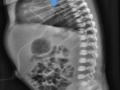

Tomography with vesicovaginal fistula